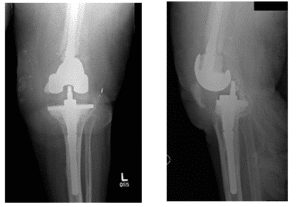

Le patient est venu avec des radiographies pour examen, comme indiqué ci-dessous. Lors de l’examen, le patient ressentait de la douleur et on lui a finalement conseillé de subir une arthroplastie totale du genou gauche (ATG) Chirurgie de reconstruction. Toutes les alternatives et options ont été longuement discutées avec le patient.

Les radiographies montrent une ostéolyse de la composante fémorale et tibiale de la prothèse gauche de l’ATG

Il existe également une calcification capsulaire et une distension capsulaire ainsi qu’un amincissement sévère du cortex autour de la face supérieure du fémur. Les flèches montrent l’ostéolyse de l’os.

Les radiographies montrent des changements préopératoires de la reconstruction de l’ATG gauche